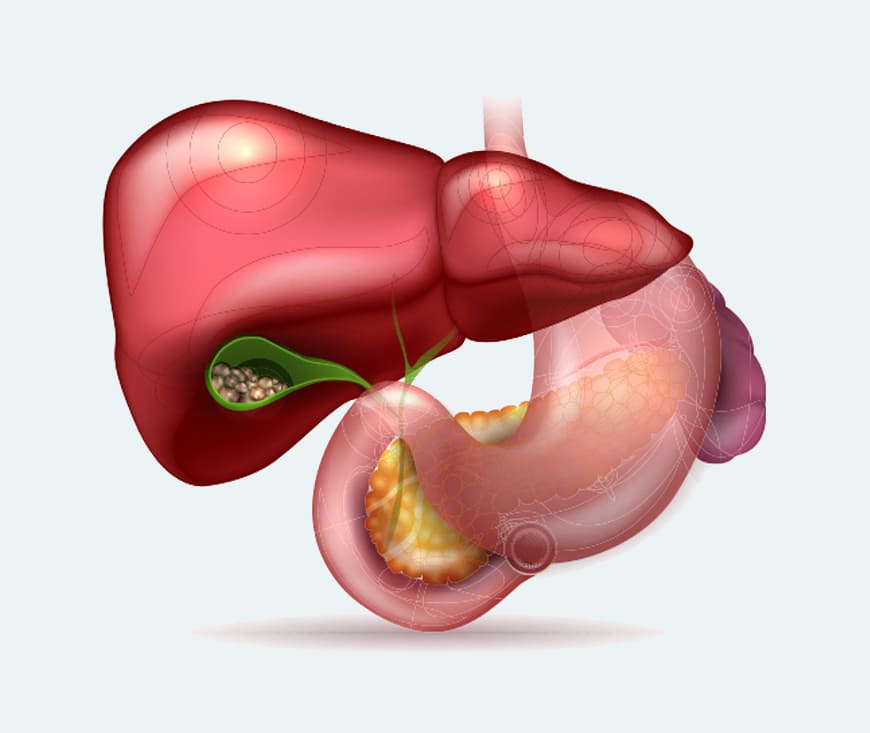

Gallstones are solid particles that form in the gallbladder, often causing pain or digestive issues. Treatment options include medications to dissolve small stones or surgery to remove the gallbladder (cholecystectomy) for more severe cases. Maintaining a healthy diet, rich in fiber and low in fats, can help prevent recurrence. If symptomatic, consult a healthcare provider for personalized care

Pancreatitis is inflammation of the pancreas, often caused by gallstones, heavy alcohol

use, or high triglyceride levels. Acute pancreatitis requires hospitalization for

fluids, pain relief, and sometimes antibiotics. Chronic pancreatitis may involve enzyme

replacements, pain management, and lifestyle changes like a low-fat diet and avoiding

alcohol.